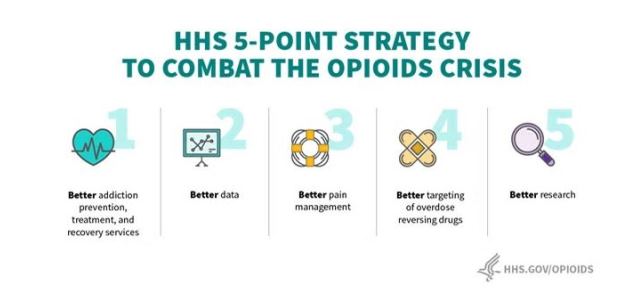

"Addressing the opioid crisis with all the resources possible and the best science we have is a top priority for President Trump and for everyone at HHS," said HHS Secretary Alex Azar. "The more than $1 billion in additional funding that we provided this week will build on progress we have seen in tackling this epidemic through empowering communities and families on the front lines."